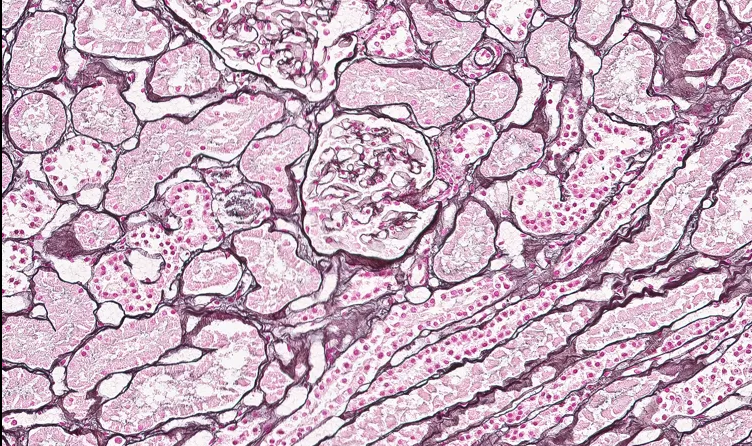

1) 슬라이드 스캐너 (Philips)

- 조직 검체의 수술병리검사 슬라이드를 디지털 이미지로 전환해 병리의사가 검토 및 분석

- 2018년 FDA 승인 받음